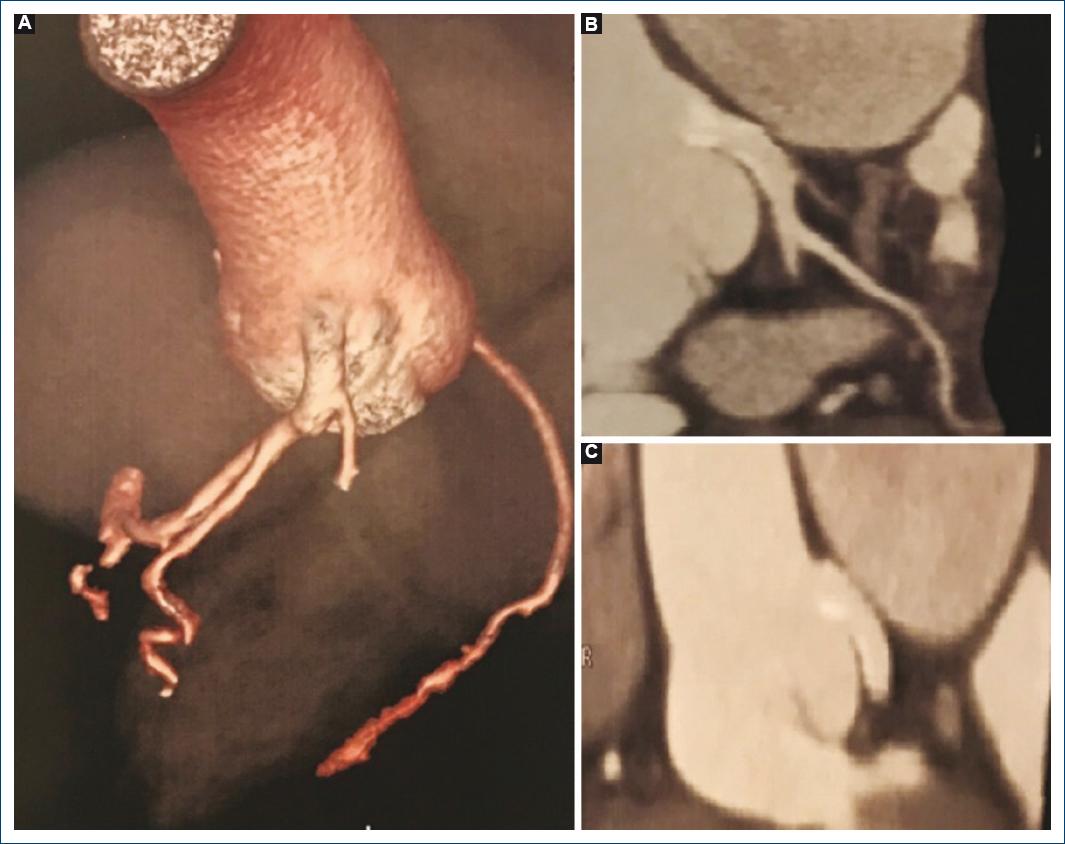

Existen escasos datos con respecto a la evolución y la tasa de complicaciones de estos procedimientos a largo plazo. En el caso informado, ante la ausencia de síntomas referidos por la paciente luego del procedimiento, se realizó cada año una angiotomografía de tórax, la última tres años después del implante del stent, sin hallar evidencia de reestenosis ni compresión extrínseca (Fig. 2).

Figura 2 A: angiotomografía de tórax, reconstrucción tridimensional: se observa conservado el calibre del stent colocado en el tronco de la arteria coronaria izquierda, sin signos de reestenosis o compresión. B: angiotomografia de tórax: se presentan dos cortes en los que se visualiza la ausencia de complicaciones relacionadas con el stent implantado; el tronco de la coronaria izquierda muestra un trayecto anómalo debido a la dilatación de la arteria pulmonar.

A modo de conclusión, la compresión extrínseca del tronco de la coronaria izquierda por la dilatación de la arteria pulmonar es una causa cada vez más reconocida de angina u otras complicaciones más graves en pacientes con diagnóstico de hipertensión pulmonar. Su identificación debe ser precisa a través de la sospecha clínica y la utilización de los métodos complementarios ya comentados. El tratamiento de primera línea es el endovascular, considerado el alto riesgo quirúrgico de estos pacientes. El seguimiento realizado a tres años desde el procedimiento sin evidenciar complicaciones tiene la intención de establecer un aporte en relación con la seguridad de esta terapéutica a largo plazo.